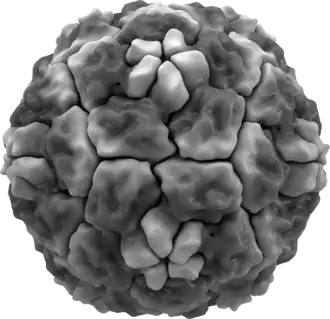

Superficie molecular de un rinovirus que muestra las espículas proteínicas. | ||

Los rinovirus tienen un ARN de cadena simple con polaridad de sentido positiva y genomas entre 7.2 y 8.5 kilobases de longitud. En el extremo 5′ de su genoma está una proteína codificada por el virus, y como en el ARN de mamífero existe una cola de poliadenilación en posición 3′. Las proteínas estructurales se codifican en la región 5′ del genoma y las no estructurales al final. Esta circunstancia se da también en todos los picornavirus. Las partículas virales carecen de cápsula viral y poseen estructura de icosaedro.

Los rinovirus están compuestos por una cápside que contiene cuatro proteínas virales: VP1, VP2, VP3 y VP4.[1][2] VP1, VP2, y VP3 forman la mayor parte de la cápside proteínica.

La VP4, que posee un tamaño mucho menor tiene una estructura mucho más extensa y se sitúa en la interfaz entre la cápside y el genoma de ARN. Hay 60 copias de cada una de estas proteínas que se ensamblan en un icosaedro. La principal defensa contra la infección son los anticuerpos, situándose los epitopos en las regiones VP1-VP3.